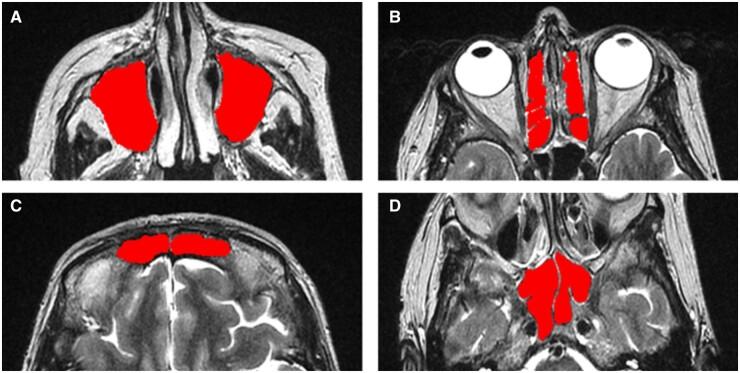

Nasal, paranasal sinus and mucosal disorders are common symptoms in autoimmune rheumatic diseases. Soft tissue changes and fluid accumulation in the osteomeatal complexes and paranasal sinuses manifest as opaqueness on radiological images which can be assessed using visual scoring and computational methods on CT scans, but their results do not always correlate. Using MRI, we investigate the applicability of different image analysis methods in SLE.

We assessed paranasal sinus opaqueness on MRI from 51 SLE patients, using three visual scoring systems and expert-delineated computational volumes, and examined their association with markers of disease activity, inflammation, endothelial dysfunction and common small vessel disease (SVD) indicators, adjusting for age and sex-at-birth.

The average paranasal sinus volume occupation was 4.55 (6.47%) [median (interquartile range) = 0.67 (0.25-2.65) ml], mainly in the maxillary and ethmoid sinuses. It was highly correlated with Lund-Mackay (LM) scores modified at 50% opaqueness cut-off (Spearman's ρ: 0.71 maxillary and 0.618 ethmoids, P < 0.001 in all), and with more granular variations of the LM system. The modified LM scores were associated with SVD scores (0: B = 5.078, s.e. = 1.69, P = 0.0026; 2: B = -0.066, s.e. = 0.023, P = 0.0045) and disease activity (anti-dsDNA: B = 4.59, s.e. = 2.22, P = 0.045; SLEDAI 3-7: 2.86 < B < 4.30; 1.38 < s.e. < 1.63; 0.0083 ≤ P ≤ 0.0375). Computationally derived percent opaqueness yielded similar results.